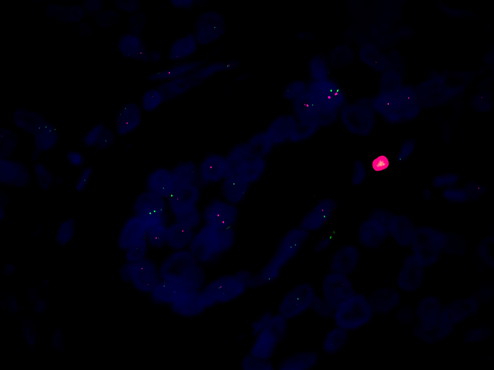

隨著癌癥的發病率不斷攀升,癌癥早篩已經成為了醫學界的熱門話題。熒光顯微鏡MF43-N觀察 HER-2 是癌癥早篩中的關鍵指標,下面我們來深入了解一下。

HER-2 是一種蛋白質,通常在乳腺癌和其他癌癥中過度表達。通過檢測 HER-2 的表達水平,可以早期診斷乳腺癌,并幫助醫生制定合適的治療方案。

FISH熒光原位雜交是一種先進的顯微鏡技術,可以用于檢測 HER-2 的表達水平。在癌癥早篩中,熒光顯微鏡MF43-N可以用于對熒光染色的細胞進行觀察,然后通過觀察細胞中不同信號點的數量和分布來檢測 HER-2 的表達水平。這種技術可以有效地檢測出 HER-2 過度表達的細胞,為癌癥的早期診斷提供重要依據。

總結起來,熒光顯微鏡MF43-N結合FISH熒光原位雜交技術觀察 HER-2,是癌癥早篩中的有效技術。通過使用這種技術,可以有效地檢測出癌癥的早期跡象,從而提高患者的生存率。